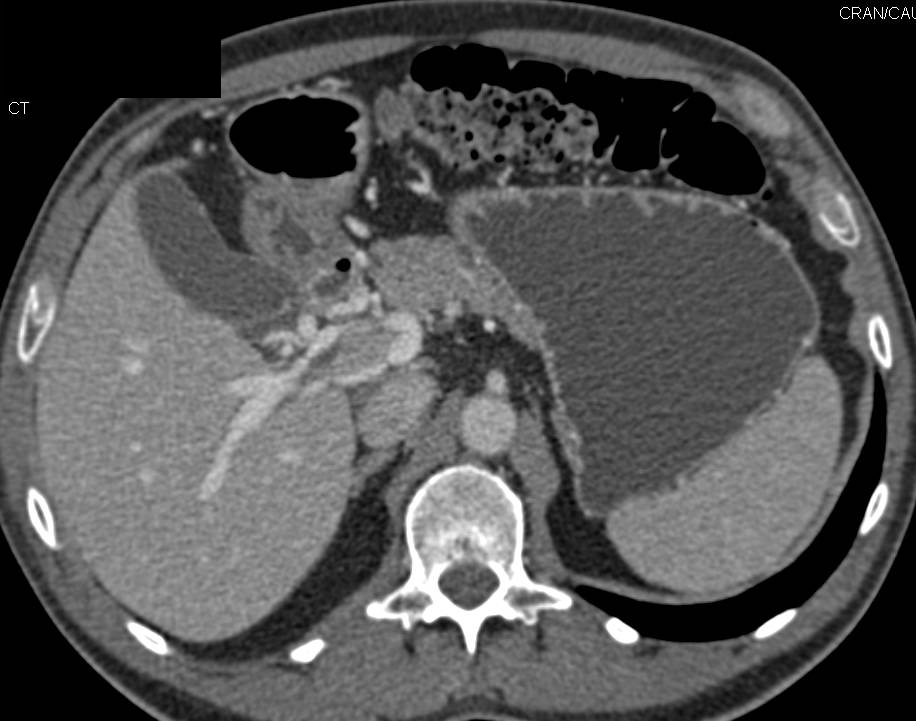

CTA of Circle of Willis Comparing Dual Energy Bone Removal Versus Autobone Removal. Dual Energy is Ideal for Base of Skull Editing